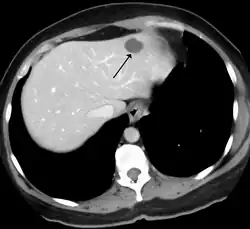

| Metástases de um adenocarcinoma de pâncreas ao fígado. | |

A maioria dos cânceres de fígado são metástases de outros tumores, geralmente de origem abdominal como o câncer de cólon, câncer de ovário e câncer renal, mas também são comuns os originados de um câncer de mama e câncer de pulmão.